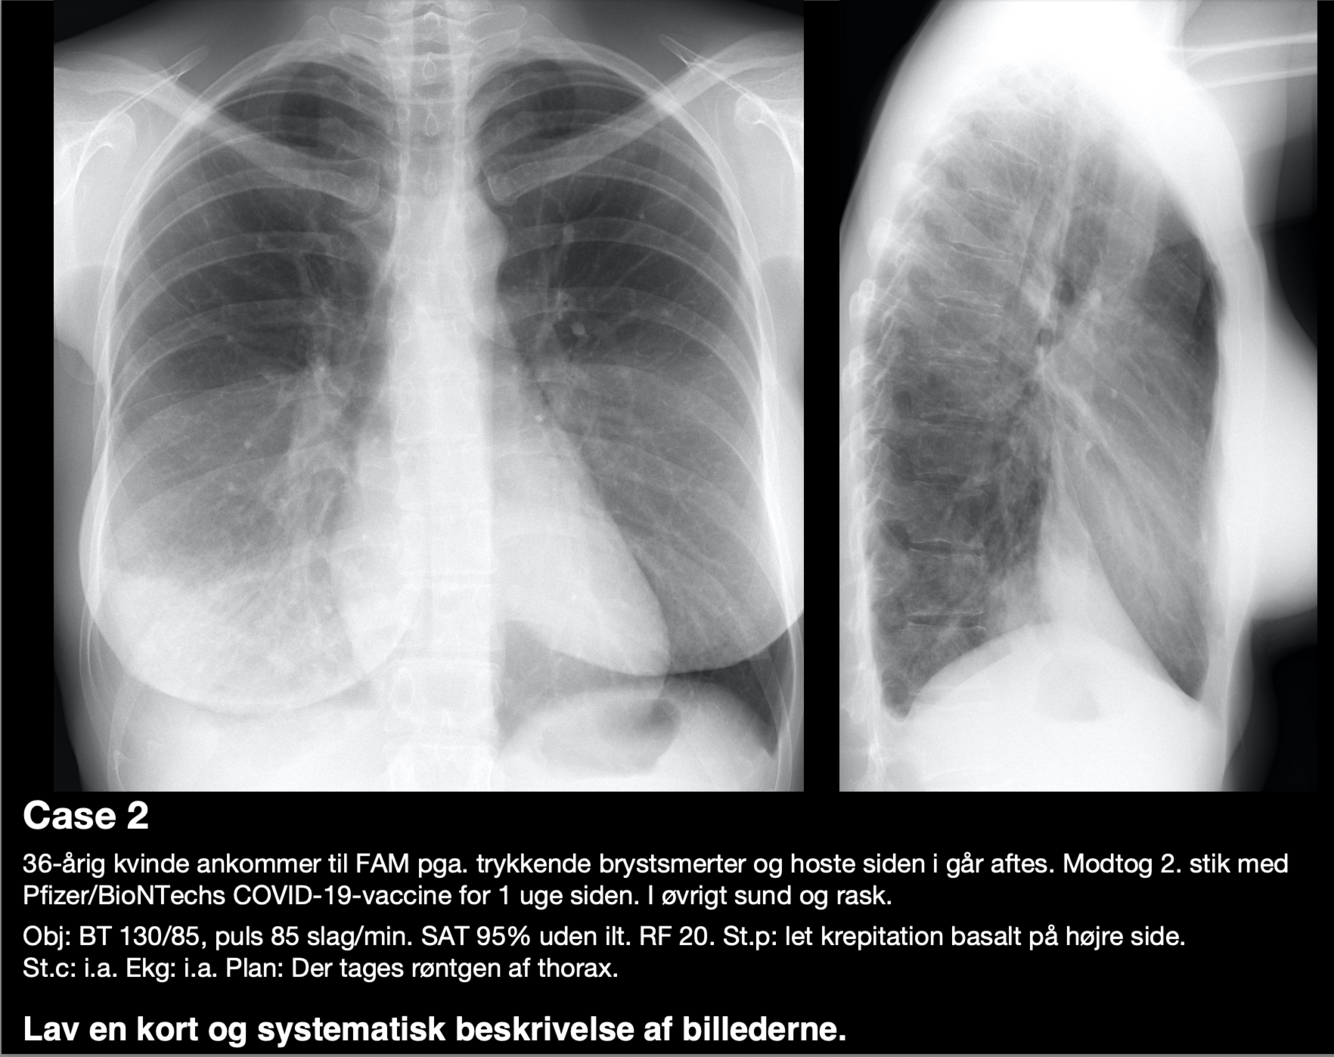

Diagnose?

A

Højresidig basal pneumoni